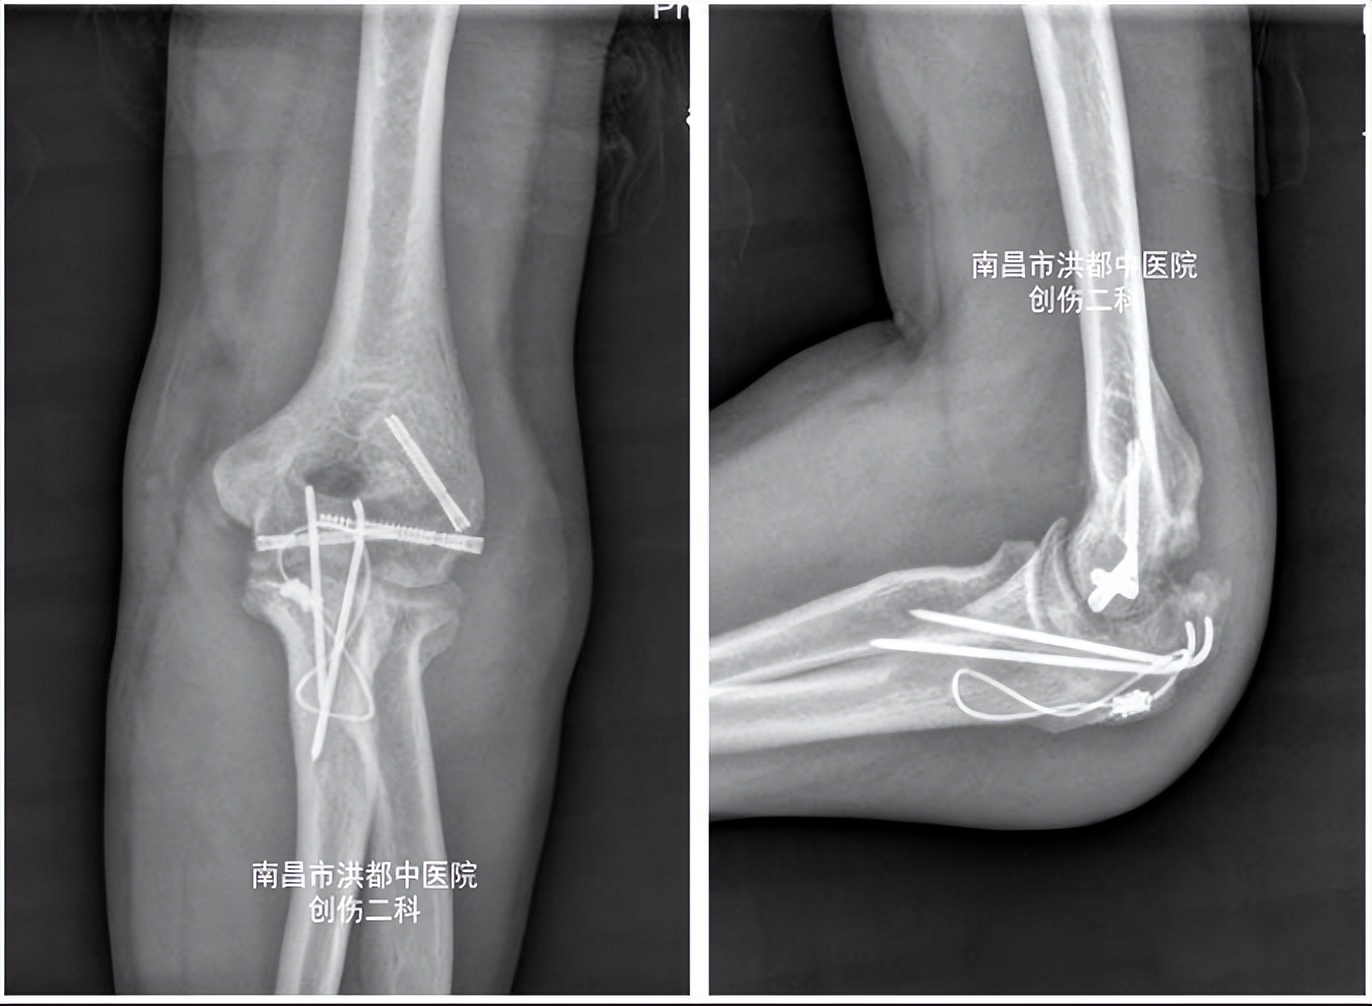

术前DR

上饶市鄱阳县35岁的徐女士,一年前因 左尺骨鹰嘴骨折、左肱骨髁部骨折 做了内固定手术,13个月后,她来到南昌市洪都中医院创伤二科,希望取出内固定物。然而,医生在门诊为徐女士检查时发现,由于术后康复训练不到位,其肘关节功能恢复不佳,不能完全弯曲和伸直,屈伸活动受限。

经摄片检查发现,徐女士左肘关节周围有大量异位骨化及增生组织,遂拟“ 1.左肱骨髁部、尺骨鹰嘴骨折术后,2.左肘关节僵硬 ”收治入院。